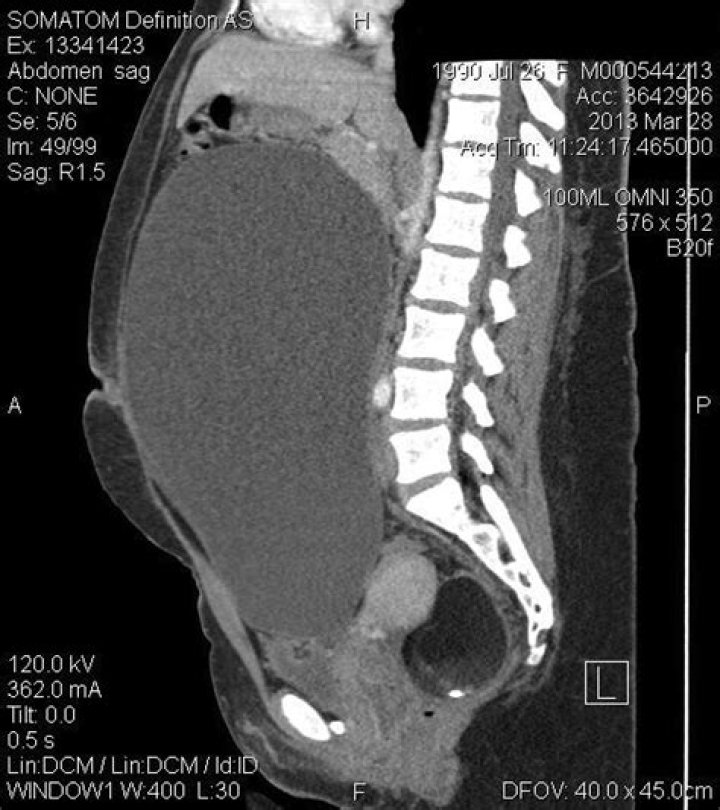

What size is a giant ovarian cyst?

Introduction. Female pelvic cysts mostly come from the ovary and are asymptomatic when they are small. The symptoms appear when they reach enormous dimensions. Giant ovarian cysts (GOCs) are tumors larger than 10 cm in diameter or those cysts reaching above the umbilicus (1).

Is a 15 cm ovarian cyst large?

Giant ones (> 15 cm) are very rare and can be symptomatic. Because of the associated symptoms such as mass effect and the doubt of ovarian malignancy, they usually require resection (mostly as oophorectomy) [1]. Most women with dermoid cysts are asymptomatic. If present, symptoms depend upon the size of the mass.